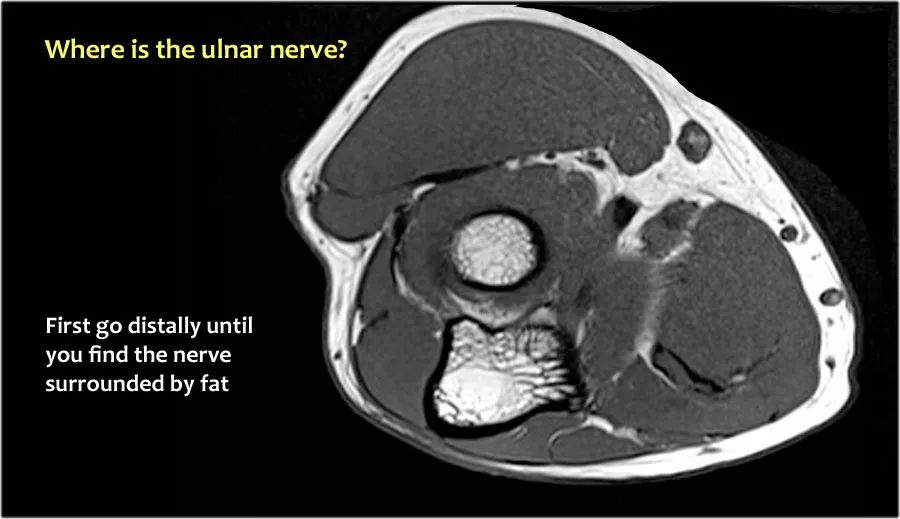

当他们将尺神经带出隧道时,他们把它放在哪里,它可以是皮下,肌肉下或肌肉内。

因此,当我们回到图像时,您会发现很难找到神经。任何这些皮下结构都可以是转位神经。一种方法是远端跟随结构,直到你发现远端的尺神经位于由脂肪包围的前臂近端的正常位置。然后当你向近端跟随它时,你会发现这是皮下移位。

在这种情况下,有神经炎。神经增大。在T2W图像上有高信号。另一个标志是在矢状图像(箭头)上看到的束的不均匀扩大。